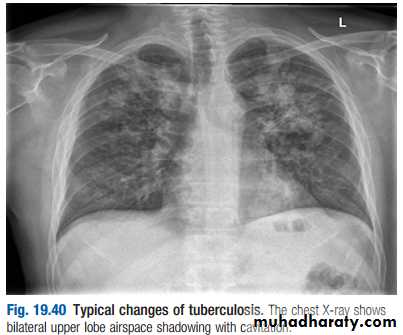

Radiological changes include ill-defined opacification in one or both of the upper lobes, and as progression occurs, consolidation, collapse and cavitation develop to varying degrees

It is often difficult to distinguish active from quiescent disease on radiological criteria alone, but the presence of a miliary pattern or cavitation favours active disease. In extensive disease, collapse may be marked and results in significant displacement of the trachea and mediastinum. Occasionally, a caseous lymph node may drain into an adjoining bronchus, leading to tuberculous pneumonia.